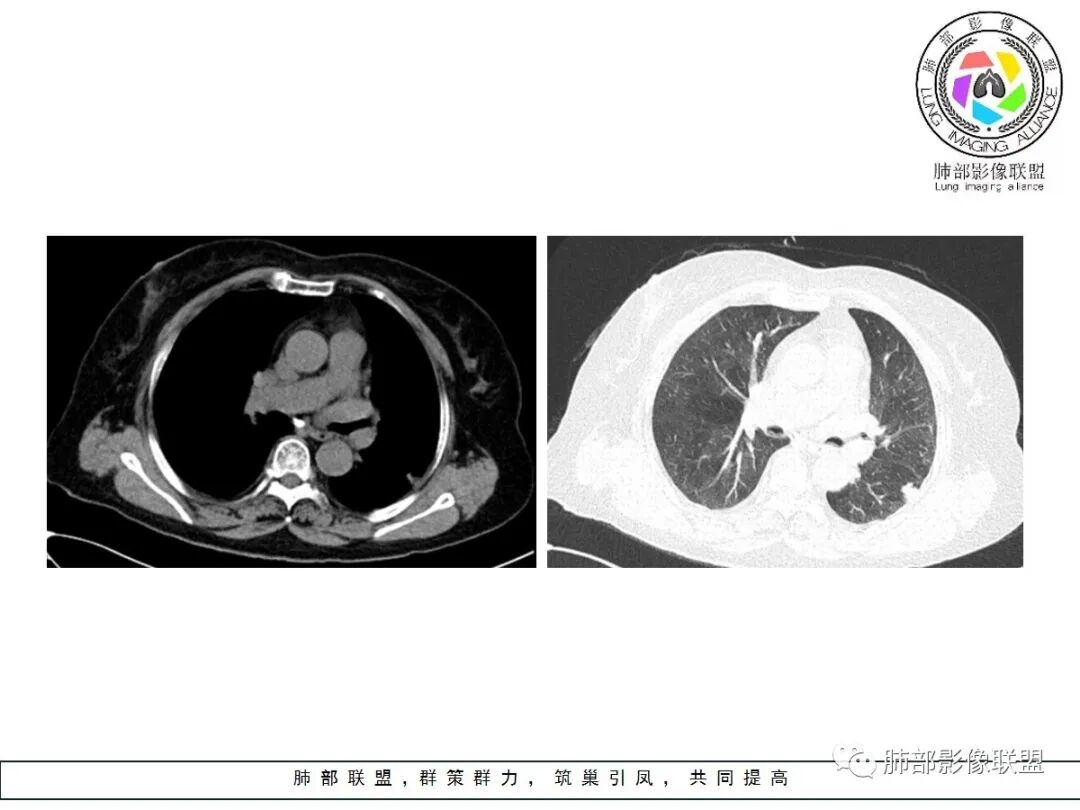

左肺下叶的不规则病灶,有恶性征象,有深分叶,病灶有支气管进入截断了,病灶里支气管扩张;良性征象有平直征,病灶强化明显,脂肪间隙存在,肉芽肿病变鉴别肌纤维母细胞瘤

老年女性,左肺下叶的不规则病灶,深分叶,病灶有支气管进入截断,血管集束,斜裂牵拉,但胸膜干净,有平直征,病灶强化明显,最后还是考虑恶性,鉴别隐球

左肺下叶背段胸膜下不规则结节,有良性征象:有平直、U形凹陷,胸膜下脂肪间隙清晰,明显强化;又有些恶性征象:有分叶,叶间胸膜牵拉。

有些纠结,还是考虑恶性(腺癌可能)> 炎性肉芽肿

临床无特殊。良性征像:冠状位方正,直边征,横断位略呈三角形,尖端指向肺门。恶性征像:小结节堆积样改变,轻度强化,增加20hu左右。横断位多分叶、毛刺。斜裂牵拉内收,胸膜被掀起伴局部少量积液,病灶底部似凸于胸膜外。腺癌与炎性肉芽肿病变的鉴别。强化方式及周边情况,结核可能小。收缩力很大,把腺癌放第一吧。

老年,实验室无异常,左肺结节,同胸膜宽基底相连,密度均,胸膜下脂肪存在,增强明显不均匀强化,考虑良性病变,炎性肉芽肿,结核,隐球。

良性征象(宽基底与胸膜相连,没有明显胸膜凹陷与微积液,收缩力较弱,仅仅叶间胸膜略凹陷,边缘平直,U形凹陷为主,结节较散,增强动脉期强化太明显)>恶性征象(局部略有膨隆,叶间胸膜略凹陷),可疑征象(图像不太好,支气管截断不确定,分叶征象不确定,也可能是散在结节的假象,脐凹征可疑),综合考虑良性结节可能大(隐球?结核?其他炎性结节?局部肺栓塞?)腺癌待排,临床简单,穿刺一下就OK。

左肺下叶胸膜下结节,边缘部分平直收缩部分膨隆,可疑脐凹征,邻近叶间裂稍牵拉,胸膜糊墙,增强扫描均匀强化,老年女性,良恶性征象都有,平扫密度似略偏高,先考虑良性,隐球菌?一般炎性肉芽肿?腺癌待排,老年人,警惕性提高一个级别,治疗后复查或穿刺活检。

左肺下叶前基底段斑片状影,边界清楚,增强强化15Hu,冠状位矢状位,边缘平直,胸膜下胸膜外脂肪间隙尚清楚,轻度强化,先抗炎,三个月复查。

有胸膜牵拉,老年女性,角蛋白19片段稍高,部分层面稍膨隆,呈球形,边界太清楚,恶性待排除,先抗炎,三个月复查。

老年女性,左肺下叶背段一节结影,近靠胸膜下,边缘分叶状,中等强化,强化均匀,周围肺叶见小结节影,考虑结核肉芽肿,不排除恶性结节,腺癌可能。